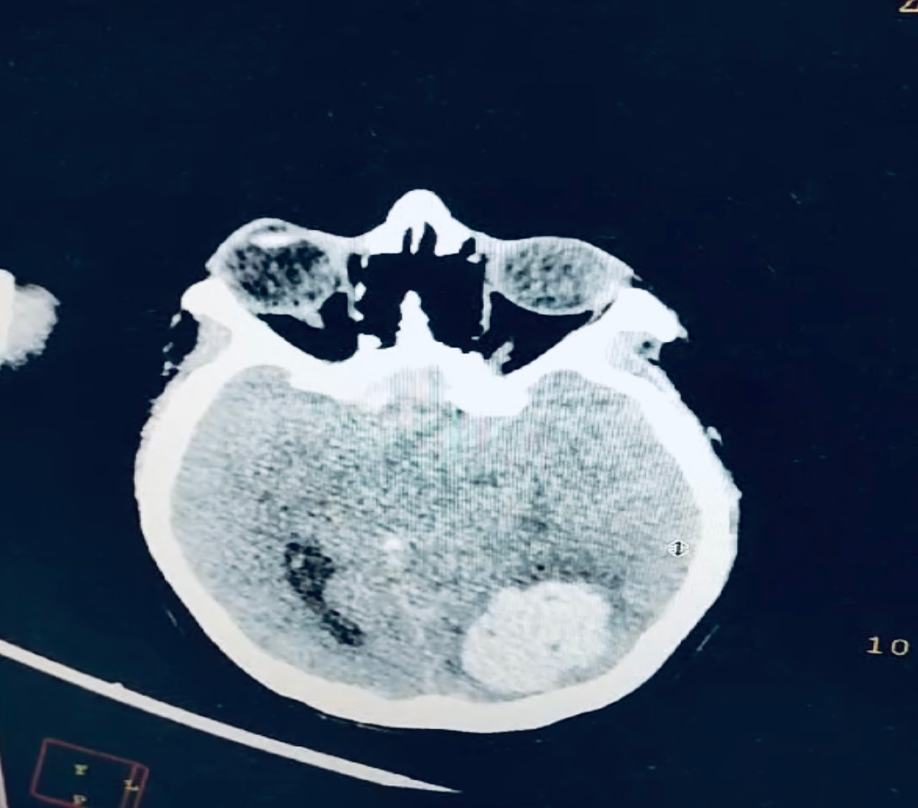

Risk factor analysis using odds ratios revealed a significant association in patients with a history of preeclampsia in a previous pregnancy (OR 12.949) and obesity (OR 1.828; p = 0.029). These results support the importance of early identification of high-risk patients during prenatal consultations (Figures 1-4 & Table 1).

Figure 4. Right parieto-occipital intraparenchymal hemorrhage secondary to eclampsia in a 17-year-old primigravida at Hospital Dr. Agustín O’Horán.